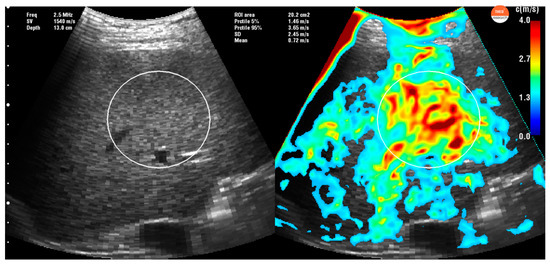

2.3. Time Harmonic Elastography Evaluation